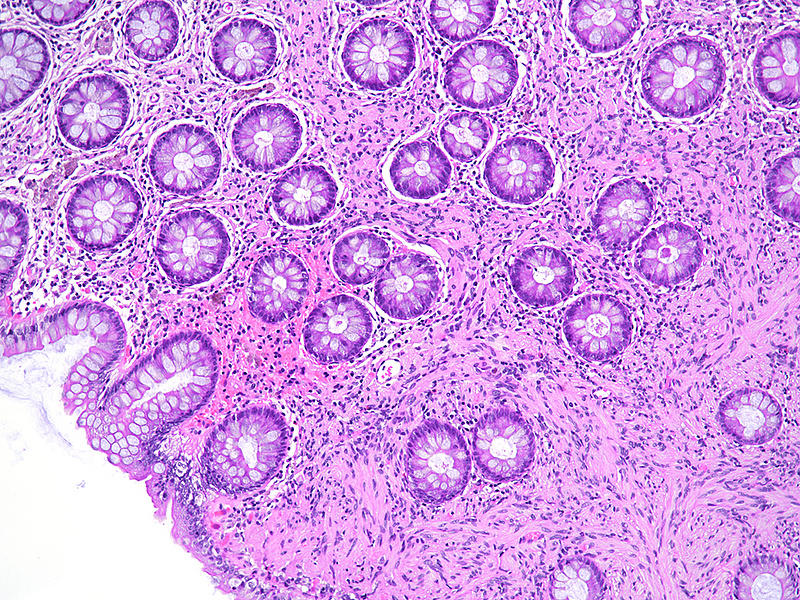

Small polyp in the sigmoid colon of a 75-year-old female.

Schwann cell hamartoma.

A dome-shaped sessile polypoid lesion with smooth glassy surface was removed from the sigmoid colon by forceps biopsy. Histology showed an expansion of the lamina propria by a diffuse proliferation of uniform bland-looking spindle cells with elongated tapering nuclei, abundant dense eosinophilic cytoplasm, and indistinct cell borders (Panels A-B). Colonic crypts were entrapped by the lesion. No nuclear atypia, pleomorphism, mitotic activity, or associated ganglion cells were observed (Panel C). The spindle cells were strong and diffusely positive for S-100 protein (Panel D).